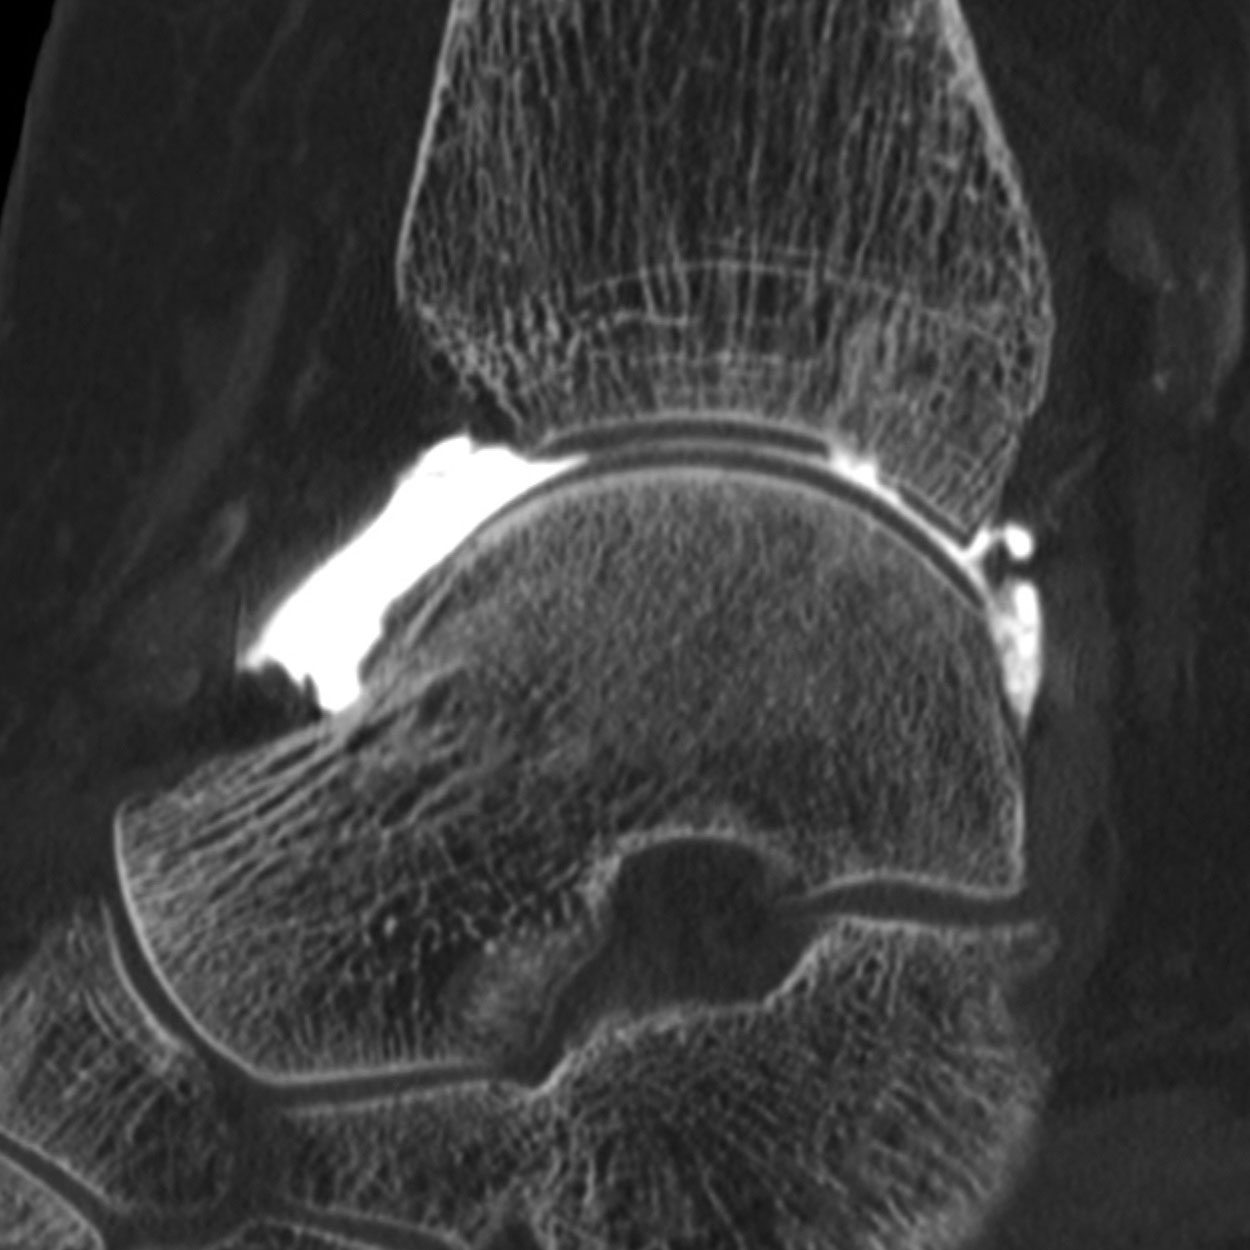

Arthroscanner images d'examen